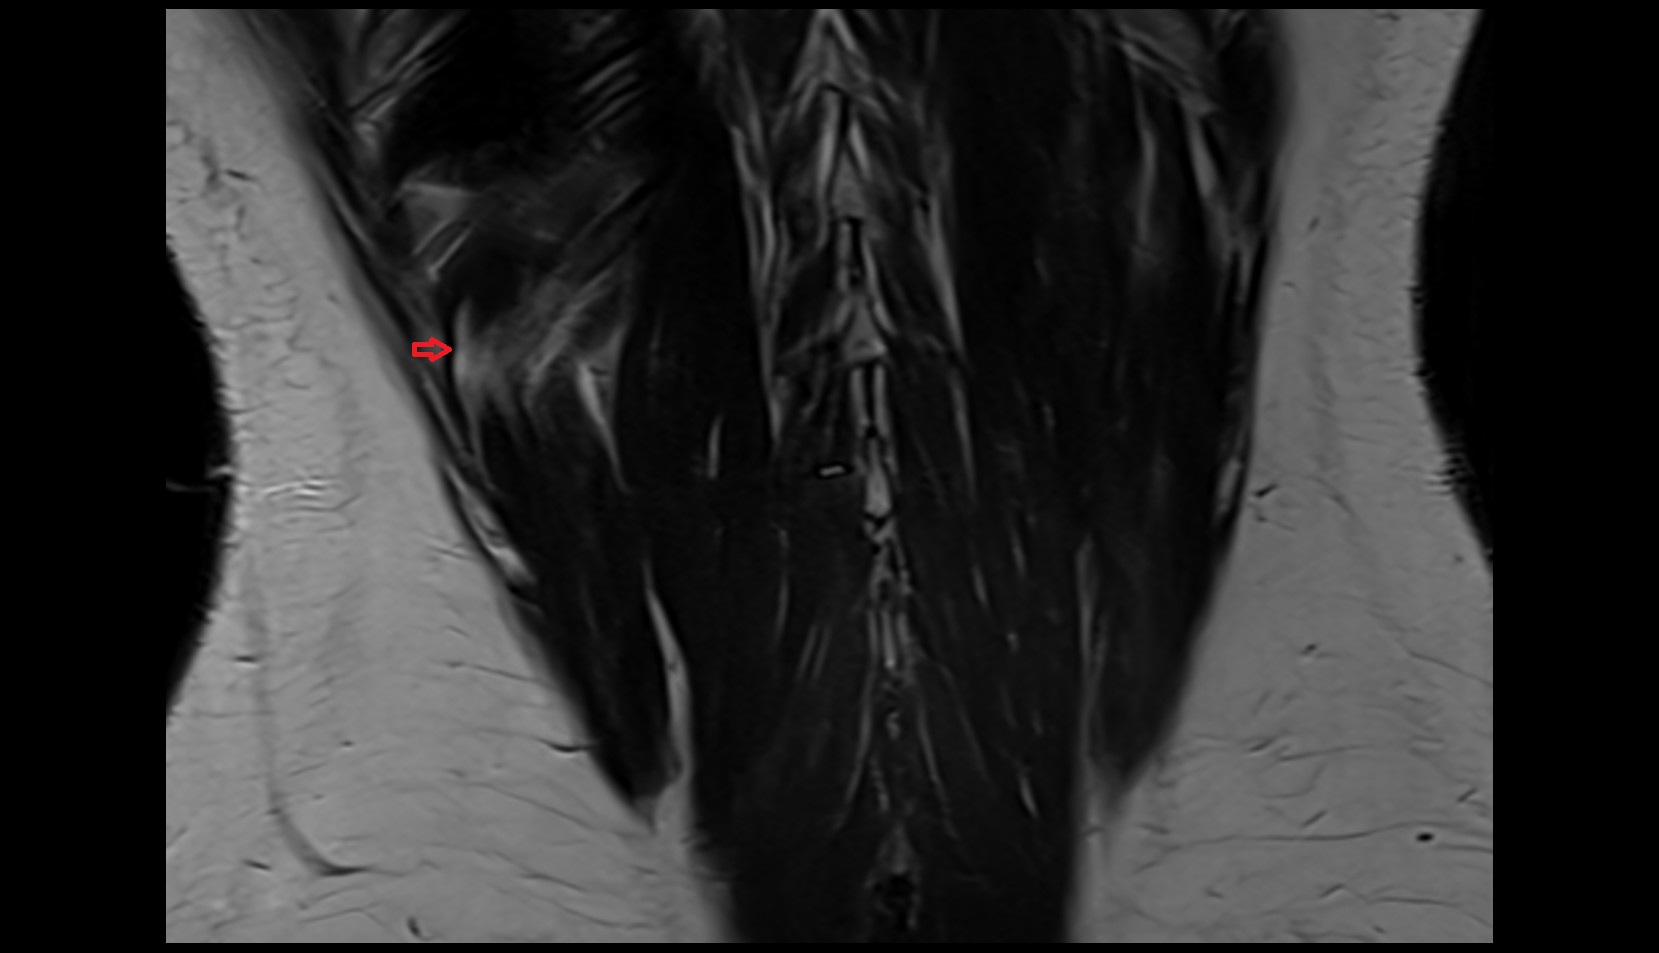

- Dorsal traversing nerve root

- Ventral traversing nerve root

- Dorsal exiting nerve root

- Ventral exiting nerve root

- Dorsal root ganglion of spinal nerve